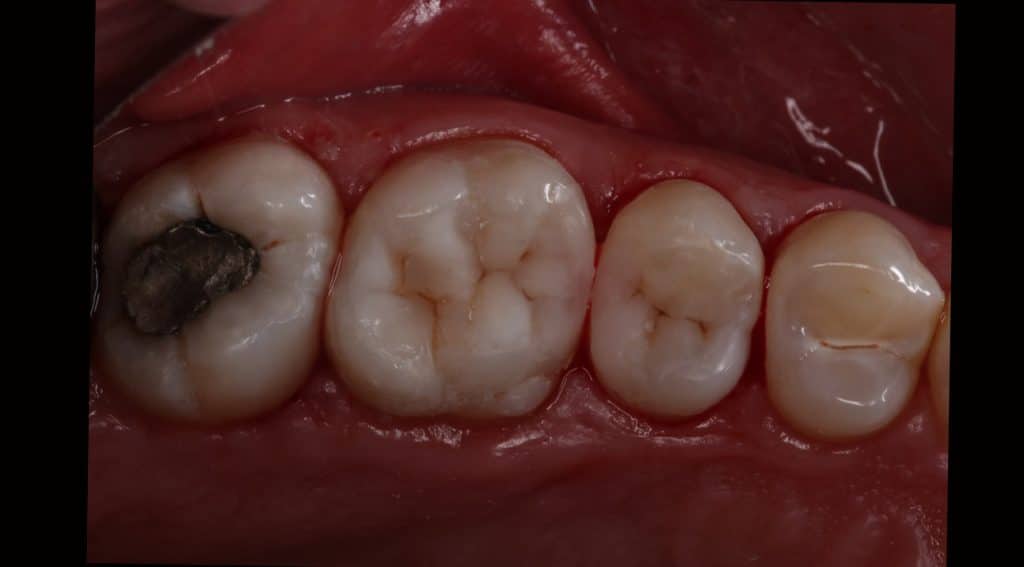

Patient complaining from bad contact and pain during cold 🥶 lasting for few second

decision made to remove old amalgam restoration .